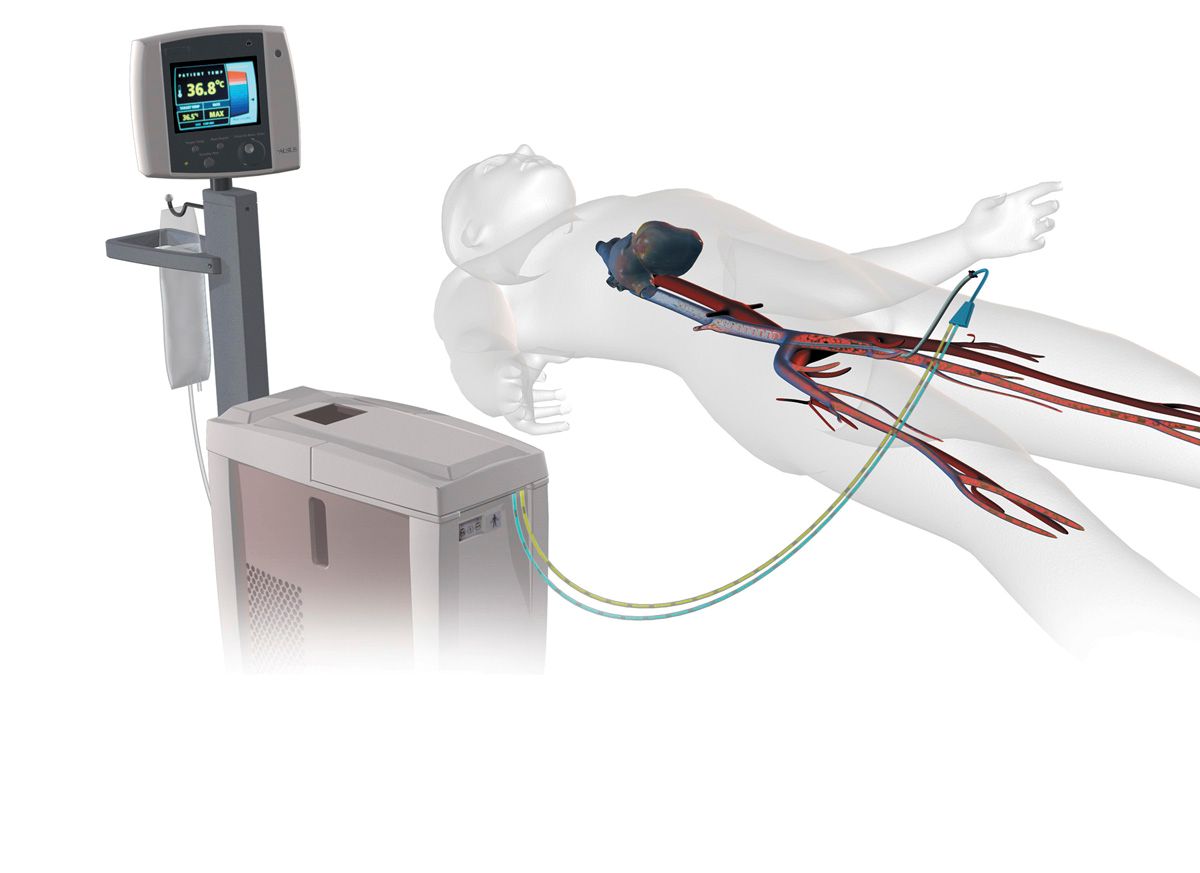

Přístroj Coolgard – tato endovaskulární metoda využívající speciální katetr, který je zaveden do dolní duté žíly cestou vény femoralis, je velmi efektivní. V uzavřeném okruhu proudí chladný fyziologický roztok, jehož teplota a rychlost cirkulace jsou řízeny extrakorporální jednotkou, která vyhodnocuje informace na základě teploty tělesného jádra. Tato teplota je měřena z teplotního čidla napojeného na speciální permanentní močový katetr (PMK). Způsob zavedení je totožný se zaváděním centrálního žilního katetru (CŽK), nezbytností je použití sterilního stolku a aseptický přístup jak ze strany lékaře, tak i ze strany všeobecné sestry. Tento speciální katetr je trojcestným CŽK, který má ovšem další vstup a výstup pro uzavřený okruh cirkulace chladicího média (fyziologický roztok 1/1; FR). Tento FR protéká v balóncích podél katetru, a tak dochází k tepelné výměně mezi chladným roztokem a krví.

Je důležité začít s chlazením pacienta co nejdříve, a proto při příjmu na intenzivní lůžko je prvním krokem podání chladných krystaloidních roztoků. Tím předcházíme prodlevě před zavedením katetru k přístroji Coolgard. Součástí každého přístroje je zjednodušený návod k použití a samotná příprava přístroje není složitá. Nutností je speciální set, na který napojíme FR o objemu 500 ml, přístroj Coolgard, má jednu hnací pumpu a samotná příprava nezabere více než 10 minut. S uvedenou endovaskulární metodou jsme schopni pacienta zchladit do 60 minut na cílovou tělesnou teplotu jádra 33–34 °C. Přístroj získává informace o teplotě jádra z teplotního čidla v permanentním močovém katetru a díky této zpětné vazbě je schopen reagovat na případnou změnu teploty. Coolgard udržuje nastavenou tělesnou teplotu s možnou odchylkou 0,2 °C. Teplota 33–34 °C je udržována 24 hodin.

Přístroj Coolgard připojený ke katetru

Zdroj: Fotoarchiv firmy Medial, 2009